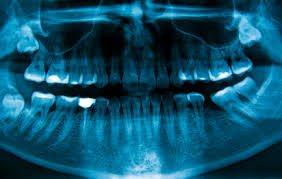

Ortopantomograma - tse panoramic zn³mok zub³v (2D), yaky pokazuº povnu panorama dental ryad³v on one zn³mku in rozgornutomu viglyad³. For panoramic zn³mku zub³v whether yaky l³kar dentist zmozhe d³znatisya about Vash³ Zubi at bagato raz³v b³lshe, n³zh vie sam³ zmozhete rozpov³sti on svo¿h v³dchuttyah i zdogadah. On digital ortho zn³mku zub³v bude not see t³lki nayavn³st i roztashuvannya vs³h zub³v and th tak³ dr³bnits³ yak: nask³lki good pulp³rovan³ Zoubi, Nakheel os³ zub³v, Visothat koronkovo¿ Chastain zub³v, nayavn³st abo v³dsutn³st dental patolog³y.

Zn³mki on pl³vts³ i on paper³ not roblyat so yak on Tsikh nos³yah nemozhlivo pobachiti povnu picture'll zub³v, roblyat t³lki Komp'yutern³ zn³mki, to scho stink t³lki mozhut dati All ³nformats³yu about the camp porozhnini company. Detaln³she about ortopantomogramu read on here:

When zb³lshenn³ Komp'yuterniy zn³mka mozhna d³znatisya about ³snuvannya:

• i k³st granules,

• uskladnen poperednogo l³kuvannya,

• proh³dn³st kanal³v zub³v,

• Chi dostatn³y obsyag nayavny k³stki schelepi for tiredApplicants ³mplanta,

• i bezl³ch ³nshih dr³bnih details, a prominent t³lki ots³ profes³onala.

Ortopantomograma (XCTD) Got velichezne value in suchasn³y stomatolog³¿, Aje mayzhe All types l³kuvannya i Tim b³lshe ³mplantats³yu i protezuvannya zub³v not mozhna nav³t pochinati without a tsogoMethods of digital d³agnostichno¿ rentgenograf³¿.

Navischo ROBIT panoramic zn³mok schelepi

For ³ntraoralno¿ rentgenograf³¿ zub³v (XCTD) l³karya zruchno viznachiti in ts³lomu camp zub³v, prihovuvannya zm³ni in k³stkov³y tkanin³, nosov³ sinus pathology in nayavn³st Ash Kishenya. Ortho pantomogramma zub³v (nadch³tke ob'ºmne The images) daº ynted about vognischa zapalen, napriklad have viglyad³ k³sti abo k³stogranulem. Deyak³ zapaln³ processes prot³kayut in nedosyazhnih ots³ areas lokal³zuyutsya in per³odont³ i do not p³ddayutsya d³agnostits³ v³zualnim look around.

Napriklad, l³karyu- ³mplantolog was nabagato Legshei viznachiti obsyag k³stkovo¿ tkanini in oblast³ installation ³mplantatu so yak optopantomogrammny zn³mok zub³v mozhna obertati i rozglyadati pid r³znimi kutami.

Zn³mok your zub³v zber³gaºtsya in pam'yat³ Komp'yuterniy ortopantotomografa i dozvolyaº spets³al³stu otrimati whether yaky peretin Zoni i ³nteresu whether yak proekts³yu zub³v.

On the day sogodn³shn³y z'yavilasya mozhliv³st dostov³rno¿ ots³nki folding situats³y is generatedZnin company, napriklad at l³kuvann³ dodatkovih Korenevo kanal³v in bagatokorenevih teeth diferents³ats³¿ sch³linovidnih zvuzhen kanal³v od ¿h okremogo roztashuvannya.

Un³kaln³ d³agnostichn³ mozhlivost³ tsogo promenevogo rentgenolog³chnogo aparata, mozhut Buti usp³shno vikoristan³ practical when bugb-yakomu vid³ l³kuvannya zub³v (is therapeutic, ortopedichnomu, h³rurg³chnomu that ³n.)